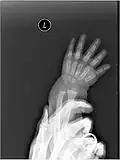

Esse caráter temporário se deve ao fato de que sua função é promover o crescimento dos ossos longos do membro. Trata-se da lâmina epifiasial, um disco cartilaginoso encontrado entre a diáfise e cada uma das duas epífises em ossos longos do indivíduo em fase de crescimento. Ela permite o aumento do comprimento do osso a partir da proliferação desse tecido cartilaginoso, seguida de sua substituição por tecido ósseo. Quando a cartilagem é totalmente ossificada, o aumento de comprimento do osso cessa. As ossificações mais tardias costumam se completar aos 20 anos de idade.[3][18]

Em bebês, nem mesmo as epífises são visualizadas inicialmente, pois têm ossificação mais tardia. Assim, em suas radiografias da mão, os espaços aparentemente vazios são ainda maiores. Só depois que as epífises se ossificam, a porção restante de cartilagem hialina (lâmina epifisial) é observada, entre cada epífise e a diáfise.[19]

Radiografia de mãos adulta e infantil. O bebê nem tem epífises ossificadas, enquanto o adulto até fechou suas lâminas epifisiais. -